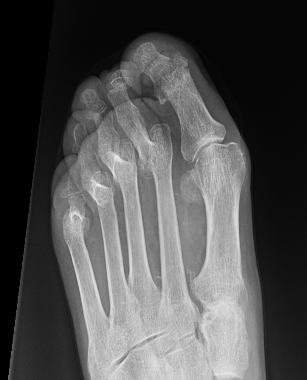

Distal metatarsal metaphyseal osteotomy (DMM)

Technique

Extra-capsular

Shortening

MIS techniques